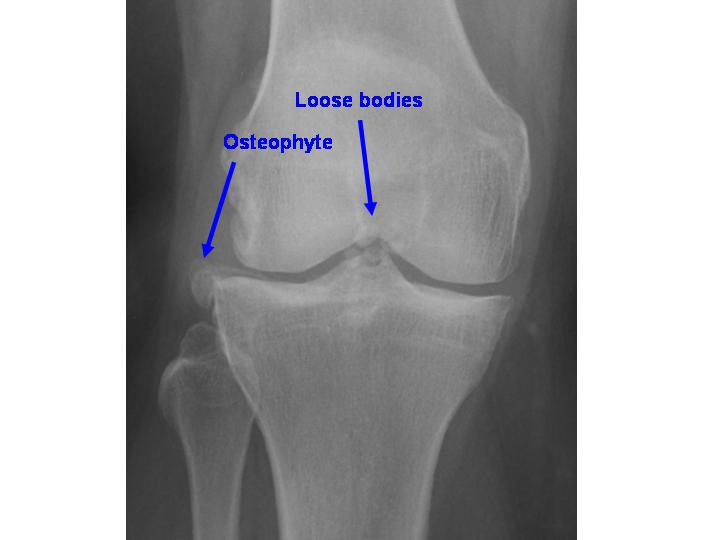

Answer: C) Osteophyte formation

Explanation: These are bony outgrowths that can occur in inflamed or degenerating joints (e.g., from osteoarthritis, joint ligament injury, ankylosing spondylitis). They can be asymptomatic or cause pain, joint deformity, tendinitis, restriction of joint movement, or compression of adjacent nerves. Visible on imaging as bony projections or spurs along the joint line.

A) is incorrect because periarticular osteopenia is typical of RA, not OA.

B) is incorrect because OA causes joint space narrowing, not widening.

D) is incorrect because erosions are characteristic of inflammatory arthritis (e.g., RA).

E) is incorrect because subchondral cysts may be present, but not in isolation, they accompany osteophytes and sclerosis and can also be present in RO.